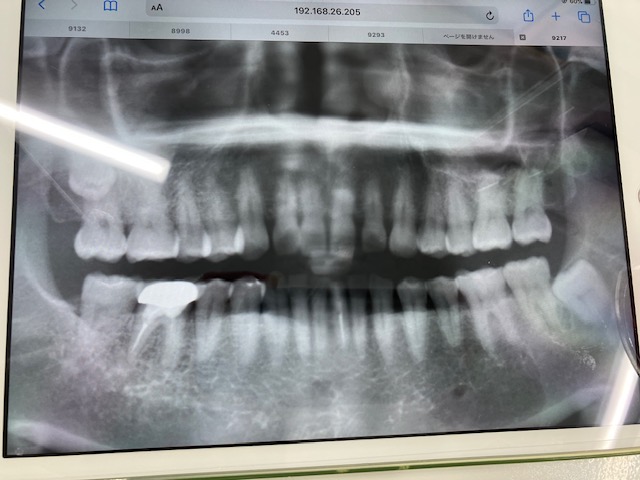

【画像】

画像1:2024年3月 ジルコニアを外して根幹治療が終わった後に撮影したもの

画像2:2025年1月に撮影したもの

画像1IMG_6187 (1).jpg 画像2IMG_6189 (1).jpg

今回個人的には3度目の根管治療は必要だと思います。

それはデンタルには写っていないものがパノラマには写っているように思えるからです。

つい先日、かかりつけ医で歯のクリーニングをした時にレントゲン写真を撮ってきたのですが

主治医からは根尖病変は無いようにみえると言われました。

(こちらに掲載した画像は 2025年1月のもの)

でも、柴田先生から

【今回個人的には3度目の根管治療は必要だと思います。

それはデンタルには写っていないものがパノラマには写っているように思えるからです。】